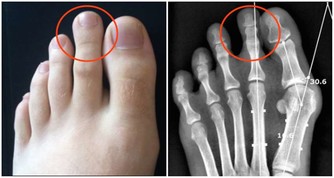

關節僵硬:它們最怕5個字

關節是骨骼之間的連接點,一旦關節出了問題,人的行動力就會受限,久之人就垮了。

關節不好的患者,對心血管系統、呼吸系統、骨骼肌系統等會造成一定影響。

因關節病長期臥床的老年人,也會引發骨質疏鬆、褥瘡、消化系統疾病。

關節在生活中最怕幾個字:

1、怕老:隨著年齡的增長,人體軟骨營養缺乏,骨骼中的無機物增多,骨骼彈力與韌性減低,易導致關節軟骨和骨退行性病變。

2、怕胖:體重增加,下肢關節承重的壓力也會增加,引起體位、步態變化,改變關節的生物力學,發生膝內翻或膝外翻,也就是常說的“O”形腿或“X”形腿。

3、怕傷:在運動、出行的過程中,如果出現急性外傷,一定要及時去醫院治療,以免留下後遺症。

不及時治療或充分休息,容易留下病根,比如“習慣性崴腳”。

4、怕勤:關節用得太狠,容易導致機械磨損,破壞軟骨。

頻繁爬山、爬樓等是非常傷害關節的。建議大家平時通過慢跑、游泳鍛煉,既不損傷關節又能鍛煉。

5、怕冷:關節受涼會引起疼痛,易導致關節僵硬。